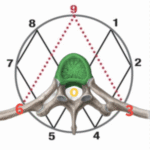

The Ribcage

Most practitioners overlook one of the most critical—and most misunderstood—elements of human physiology: the ribcage. It’s not a rigid, box-shaped frame as many assume, but a dynamic, curved, circular portal that houses and protects the body’s most vital organs. This region plays a central role in structural support, yet it’s routinely mishandled, leading to dysfunction.

Why are so many pushing the ribcage into collapse, unknowingly triggering some of the most common and frustrating symptoms? This crucial mistake is at the root of why so many patients struggle to improve, despite your best efforts.

Contrary to what’s commonly taught, the ribcage isn’t a rigid box—it’s a curved, circular, living portal that houses and protects every major organ system. It plays a central role in both respiratory and structural integrity. Yet, most techniques either ignore it or, worse, force it into dysfunction.

When you observe the anatomy of the human body, you’ll notice I’ve marked the chest cavity with “air” and the lower torso with “water.” These labels represent a key concept: the body’s natural elements and weight distribution. You can see how collapses in the lumbar spine can be weighed down by the heavier, water section of the torso. Misalignments are often attempted to be corrected by pushing kinetic energy through someone’s arms and chest cavity, basically through air and a multitude of joints. aiming to manipulate bones by brute force. But here’s the problem—this approach is both ineffective and physically damaging as well.

This is why the ribs are so sensitive in most bodies, because they are collapsed downwards and twisted at their connection points, This is why smashing any amount of pressure into them is always going to collapse them more, which is a bad idea as the chest is richly innervated by the intercostal nerves and the phrenic nerve and you risk inducing inflammation or mechanical strain in structures near the phrenic nerve (e.g., the mediastinum or pleura), indirectly affecting its function. This can result in hyperexcitability of the diaphragm, causing spasms or erratic contractions. Rib dysfunction can stimulate reflexive muscle guarding or spasms in adjacent muscles, including the diaphragm. Difficulty Breathing: A tight or spasming diaphragm can lead to shortness of breath or a sensation of not being able to “catch one’s breath.” yikes… or. chest numbness as well. So Why risk it? Lets consider the physiological changes of a collapsed rib cage, Which is more prominent of a problem in the overall population than people realize.

(Notice the blue arrow in the ribs gets pushed forward and the red arrow in the ribs collapses downwards and twists at their connection points, applying force on a structure that is already collapsed like this is why the rib cage is constantly just being collapsed even more by these forces, These forces just continually pin everything else down under these counterforces of collapsing forces twisting forces and muscular resistance forces (usually from spastic forces and tension created by them.) For the practitioner, it means an uphill battle of constantly having to fight against these resistant forces (in other words going against nature.) This means an exhausting day full of straining your body against these forces and often receiving painful pokes from elbows and ribs, not to mention it is damaging to the practitioner’s knees. (Practitioner’s I’m trying to help you, Whose dumb idea was it to blast kinetic energy through the ribs and arms anyway? There has to be a more natural approach. And don’t forget for the client, this will create a lot of unwanted pressure on sensitive areas like the AC joints and can lead to rib pain, arm numbness, or worse if you collapse their ribs even more, the neck and lower back suffer as well as the muscles all attach at these connection points. Not only does this method lack results, but it also risks real injury. Let’s be clear: using the kinetic energy in this way doesn’t align or correct the body effectively, and the results if any are always just new counter measurements.